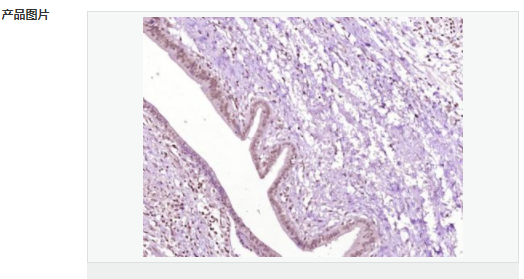

| 產品應用 | WB=1:500-2000 ELISA=1:5000-10000 IHC-P=1:100-500 IHC-F=1:100-500 IF=1:100-500 (石蠟切片需做抗原修復) not yet tested in other applications. optimal dilutions/concentrations should be determined by the end user. |

| 產品介紹 | Acts as a growth inhibitor. Can activate TP53/p53, causes G1 arrest and collaborates with CDKN2A to restrict proliferation, but does not require either protein to inhibit DNA synthesis. Redistributes CDKN2A into the nucleoplasm. Involved in maintaining chromosomal stability. There are two isoforms. Function: Acts as a growth inhibitor. Can activate p53/TP53, causes G1 arrest and collaborates with CDKN2A to restrict proliferation, but does not require either protein to inhibit DNA synthesis. Redistributes CDKN2A into the nucleoplasm. Involved in maintaining chromosomal stability. Subunit: Interacts with CDKN2A and MDM2. Subcellular Location: Nucleus. Tissue Specificity: Widely expressed at low levels in most tissues, with highest levels in pancreas, lung and liver. Expression is decreased in primary tumors including lung, liver, breast, pancreas and kidney carcinomas, chronic lymphocytic leukemia and diffuse large B-cell lymphoma. Post-translational modifications: Ubiquitinated; mediated by MDM2 and leading to its subsequent proteasomal degradation. Similarity: Belongs to the TBRG1 family. Contains 1 FYR C-terminal domain. Contains 1 FYR N-terminal domain. SWISS: Q3YBR2 Gene ID: 84897 Database links: Entrez Gene: 84897 Human Entrez Gene: 21376 Mouse Omim: 610614 Human SwissProt: Q3YBR2 Human SwissProt: Q3UB74 Mouse Unigene: 436410 Human Unigene: 28689 Mouse Unigene: 129282 Rat Important Note: This product as supplied is intended for research use only, not for use in human, therapeutic or diagnostic applications. |